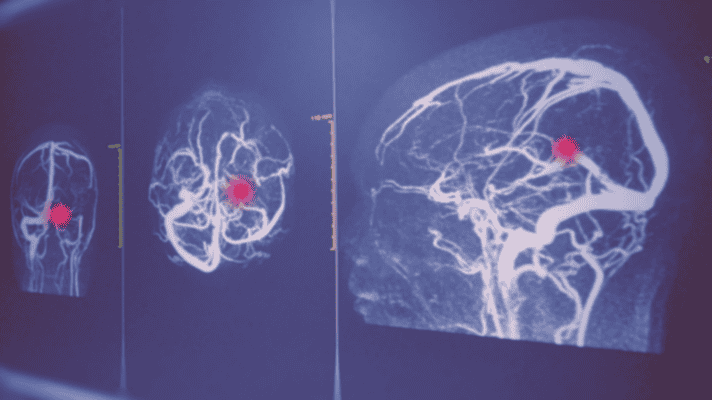

Metody wykrywania tętniaka mózgu

W większości przypadków tętniak mózgu nie daje żadnych objawów aż do momentu pęknięcia. Dlatego tak ważna jest diagnostyka obrazowa – zarówno w przypadku przypadkowego wykrycia tętniaka, jak i w ramach regularnych kontroli po leczeniu. Poznaj trzy główne metody badań, ich zasady działania, przygotowanie oraz wskazania – tak abyś mógł/mogła świadomie rozmawiać z lekarzem o swojej diagnostyce.

Angio-TK – angiografia tomografii komputerowej

Angio-TK jest najczęściej stosowaną metodą pierwszego rzutu w diagnostyce tętniaków mózgu. Jest szybka, dostępna ambulatoryjnie i charakteryzuje się wysoką czułością diagnostyczną – zgodnie z meta-analizą opublikowaną w PMC (2018) czułość angio-TK wynosi 96%, a swoistość 91%.

Dożylnie – przez wenflon w zgięciu łokciowym – podawany jest kontrast przy użyciu strzykawki automatycznej. Kontrast wypełnia tętnice i żyły, które stają się dobrze widoczne podczas skanowania głowy przez tomograf. Uzyskane obrazy są rekonstruowane do modeli 2D i 3D. Badanie jest ambulatoryjne – pacjent może wrócić do domu bezpośrednio po jego zakończeniu.